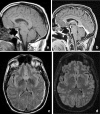

Background and purpose: The splenium of the corpus callosum is the most posterior part of the corpus callosum. Its embryological development, anatomy, vascularization, function, imaging of pathology, possible pathophysiological mechanisms by which pathology may develop and the clinical consequences are discussed.

Methods: A literature-based description is provided on development, anatomy and function. MR and CT images are used to demonstrate pathology. The majority of pathology, known to affect the splenium, and the clinical effects are described in three subsections: (A) limited to the splenium, with elaboration on pathophysiology of reversible splenial lesions, (B) pathology in the cerebral white matter extending into or deriving from the splenium, with special emphasis on tumors, and (C) splenial involvement in generalized conditions affecting the entire brain, with a hypothesis for pathophysiological mechanisms for the different diseases.

Results: The development of the splenium is preceded by the formation of the hippocampal commissure. It is bordered by the falx and the tentorium and is perfused by the anterior and posterior circulation. It contains different caliber axonal fibers and the most compact area of callosal glial cells. These findings may explain the affinity of specific forms of pathology for this region. The fibers interconnect the temporal and occipital regions of both hemispheres reciprocally and are important in language, visuospatial information transfer and behavior. Acquired pathology may lead to changes in consciousness.